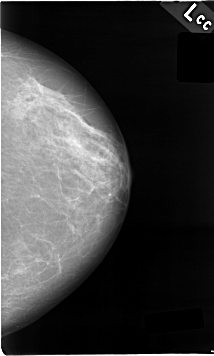

C_0009_1.LEFT_CC

LEFT_CC LINES 4624 PIXELS_PER_LINE 2776 BITS_PER_PIXEL 12 RESOLUTION 50 NON_OVERLAY

FILE: C_0009_1.RIGHT_CC.OVERLAY

TOTAL_ABNORMALITIES 1

ABNORMALITY 1

LESION_TYPE MASS SHAPE IRREGULAR MARGINS SPICULATED

ASSESSMENT 5

SUBTLETY 5

PATHOLOGY MALIGNANT

TOTAL_OUTLINES 1

BOUNDARY